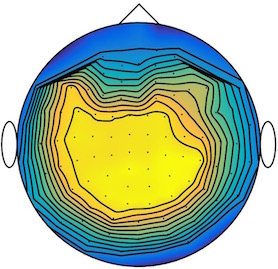

We applied our method to a magnetoencephalography (MEG) dataset. In this setup, brain activity of a subject is recorded (Elekta Neuromag, 306 sensors of which 204 planar gradiometers and 102 magnetometers, sampling frequency 1000Hz) while the subject reacted to the presentation of a target stimulus by pressing either the left or the right button.

Data is preprocessed applying signal space separation correction, interpolation of noisy sensors, and realignment of data into a subject-specific head position (MaxFilter, Elekta Neuromag). The signal was then filtered (low pass 40HZ), and artifacts such as blinks and heartbeats removed thanks to Signal-Space Projection using the Brainstorm software222http://neuroimage.usc.edu/brainstorm. The samples we used for our barycenter computations are an average of the norm of the two gradiometers for each channel from stimulation onto 50ms and the classes were left or right button.

| Class 1 | Class 2 | ||||||

|

|

|

|

|

|

|

|

| Sample 1 | Sample 2 | Sample 3 | Mean | Sample 1 | Sample 2 | Sample 3 | Mean |

|

|

|

|

|

|

|

|

This results in two classes of recordings, one for each pressed button. We aim at computing a representative activity map for each class using Wasserstein barycenters. For each class we have recordings each having samples located on the vertices of an hexahedral mesh of a hemisphere (corresponding to a MEG recording helmet). These recorded values are positive by construction, and we rescale them linearly to impose . Figure 6, top row, shows some samples from this dataset, displayed using interpolated colors as well as iso-level curves. The black dots represent the position of the electrodes on the half-sphere of the helmet, flattened on a 2-D disk.

We computed TV-regularized barycenters independently for each class by solving (16) with the TV regularization using the projected gradient descent method (22). We used a squared Euclidean metric (24) on the flattened hemisphere. Since the data is defined on an irregular graph, instead of (23), we use a graph-based discrete gradient. We denote the graph which connects neighboring electrodes. The gradient operator on the graph is

The total variation on this graph is then obtained by using , the norm, i.e. we use in (23).

Figure 6 compares the naive barycenters (i.e. the usual mean), barycenters obtained without regularization (i.e. ) and barycenters computed with an increasing regularization strength . The input histograms being very noisy, the use of regularization is important to make the area of significant activity emerge from the noise. The use of a TV regularization helps to keep a sharp transition between active and non-active regions.